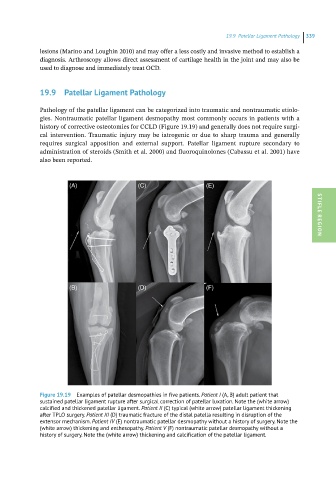

Figure 19.19 Examples of patellar desmopathies in five patients. Patient I (A, B) adult patient that

sustained patellar ligament rupture after surgical correction of patellar luxation. Note the (white arrow)

calcified and thickened patellar ligament. Patient II (C) typical (white arrow) patellar ligament thickening

after TPLO surgery. Patient III (D) traumatic fracture of the distal patella resulting in disruption of the

extensor mechanism. Patient IV (E) nontraumatic patellar desmopathy without a history of surgery. Note the

(white arrow) thickening and enthesopathy. Patient V (F) nontraumatic patellar desmopathy without a

history of surgery. Note the (white arrow) thickening and calcification of the patellar ligament.

Pathology of the patellar ligament can be categorized into traumatic and nontraumatic etiolo -

gies. Nontraumatic patellar ligament desmopathy most commonly occurs in patients with a

history of corrective osteotomies for CCLD (Figure 19.19) and generally does not require surgi -

cal intervention. Traumatic injury may be iatrogenic or due to sharp trauma and generally

requires surgical apposition and external support. Patellar ligament rupture secondary to

administration of steroids (Smith et al. 2000) and fluoroquinolones (Cabassu et al. 2001) have

also been reported.